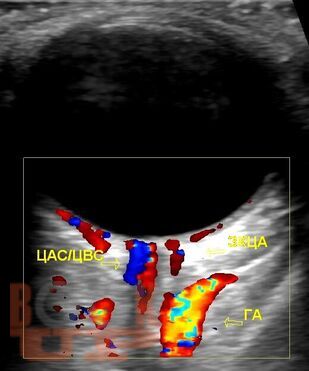

Пособие посвящено ультразвуковой диагностике заболеваний глазного яблока, орбиты. Описана методология ультразвукового исследования глазного яблока и орбиты в В-режиме, режиме допплерографии. Приведены диагностические алгоритмы использования ультразвука в верификации заболеваний глазного яблока, орбиты.

Отдельное внимание уделено клиническим случаям, представлены сонограммы с описанием ультразвуковой картины патологических изменений глазного яблока и орбиты.